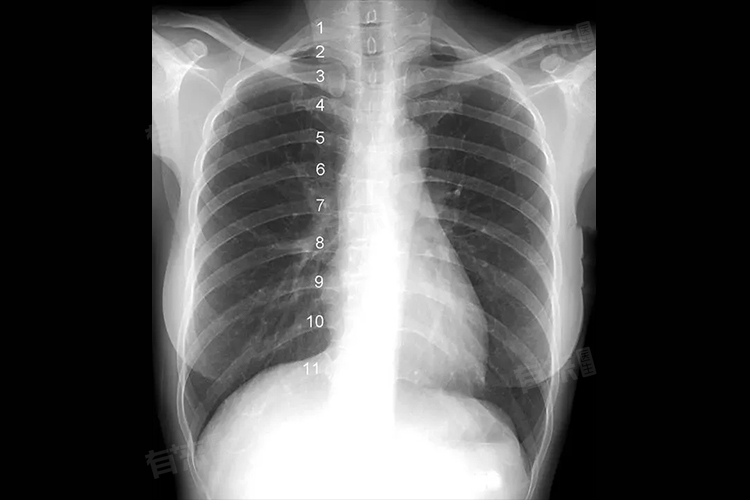

右肺见斑片状高密度影是在胸部影像学检查中呈现出的表现,指的是右肺区域出现了比正常肺组织密度更高的斑片状阴影,其病因包括肺挫伤、肺部感染、肿瘤等,需要及时配合医生进行治疗。

- 影像学检查:胸部X光、CT是发现右肺斑片状高密度影的主要手段。CT检查能够更清晰地显示病变的细节、范围和性质,有助于进一步明确诊断。